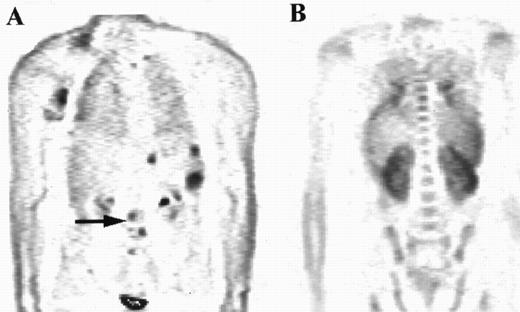

The distribution of uptake within the marrow was noted. Focal abnormality is seen within the lumbar spine in patient A (arrow), while patient B has diffuse marrow abnormalities.

All four patients who had focal marrow disease on the PET scan but histologically normal iliac crest marrow had normal FDG uptake at the site of the biopsy. In that respect these patients could be classed as concordant. In one of these patients subsequent biopsy of a “hot spot” localized within the left humeral head confirmed nodular sclerosing HD in the marrow (Fig 4). The other 3 patients did not have additional biopsies, but the 2 patients with high-grade NHL had other evidence of stage IV disease, with pulmonary lymphoma deposits shown by PET and CT.

PET images of a patient with areas of focal increased uptake in marrow, most notably in the left humerus (solid arrow, A) and in the thoracic spine (B). The marrow was not diffusely abnormal and much of the axial skeleton exhibited FDG uptake less than in liver (broken arrow).